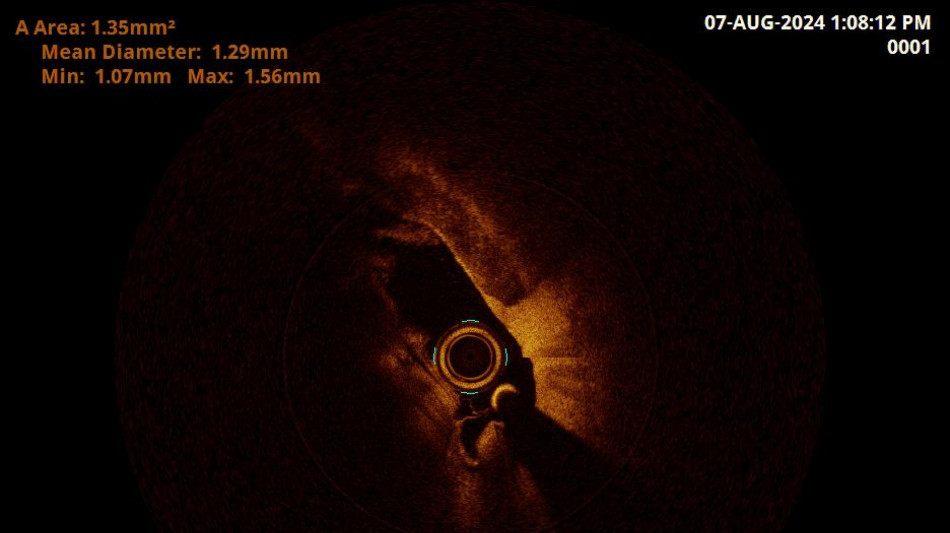

Ospedale Grosseto vede arteria vertebrale in 3D con nuovo metodo

Diagnosi unica in Italia dopo l' esperienza sulle coronarie

Una nuova tecnica diagnostica applicata all'ospedale Misericordia di Grosseto su un paziente che presentava sintomi di tipo confusionale ha permesso di effettuare un esame unico in Italia, ovvero una Oct (Optical coherence tomography) in un'arteria vertebrale. Una tecnica innovativa, spiega l'Asl Toscana Sud est, che ha consentito di ottenere un risultato diagnostico di grande interesse. Si tratta di una modalità che viene adottata di norma per gli esami delle arterie coronariche, ma che è risultata particolarmente efficace anche per l'arteria vertebrale. Il caso esaminato, che sarà oggetto anche di pubblicazione scientifica, ha riguardato un 70enne con sintomi simili allo svenimento e allo stato confusionale, già sottoposto ad AngioTac ed Ecocolor Doppler. Il paziente necessitava di un affinamento diagnostico ulteriore. Attraverso questo esame è stato possibile ottenere immagini ad altissima definizione, con un video a tre dimensioni dell'arteria utile a ricercare lesioni derivanti da placche da mettere in correlazione con la sintomatologia clinica. "Il caso studiato a Grosseto - commenta Massimo Pieraccini, direttore della Radiologia interventistica dell'ospedale Misericordia - evidenzia l'importanza della ricerca che portiamo avanti nel nostro ospedale e l'approccio multidisciplinare della nostra azione". "Siamo riusciti a portare il dispositivo all'interno dell'arteria vertebrale, superando molte difficoltà", spiega il neuroradiologo interventista Valerio Lunghi che ha eseguito la procedura. "L'implementazione di questa nuova metodica - dichiara Manuele Bartalucci, medico della Neurologia di Grosseto - ci ha permesso di prevenire l'insorgere dell'ictus, il tutto è avvenuto con la sinergia dei colleghi del Pronto soccorso che ci danno la possibilità di effettuare ricoveri brevi. Da inizio anno abbiamo gestito più di 500 percorsi 'Stroke', fibrinolisi e trattamenti endovascolari". Altri pazienti da sottoporre a questa nuova modalità interventistica sono già in programma nella lista d'attesa.